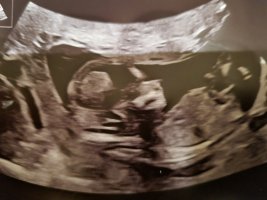

JenteVis vedlegget 417457Vis vedlegget 417458Uke 13+0. Jente eller gutt?

Tidlig jente

Jente var riktigTidlig jente![]()

Jente var riktig jaJeg gjetter også tidlig jente, nuben kan reise seg enda